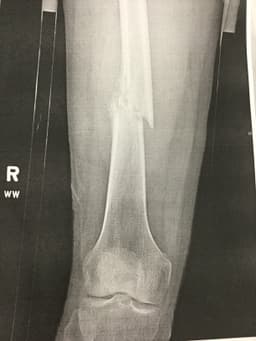

Contributor: Jared Scott, MD

Educational Pearls:

Angelini A, Trovarelli G, Berizzi A, Pala E, Breda A, Maraldi M, Ruggieri P. Treatment of pathologic fractures of the proximal femur. Injury. 2018 Nov;49 Suppl 3:S77-S83. doi: 10.1016/j.injury.2018.09.044. PMID: 30415673.

Marshall RA, Mandell JC, Weaver MJ, Ferrone M, Sodickson A, Khurana B. Imaging Features and Management of Stress, Atypical, and Pathologic Fractures. Radiographics. 2018 Nov-Dec;38(7):2173-2192. doi: 10.1148/rg.2018180073. PMID: 30422769.